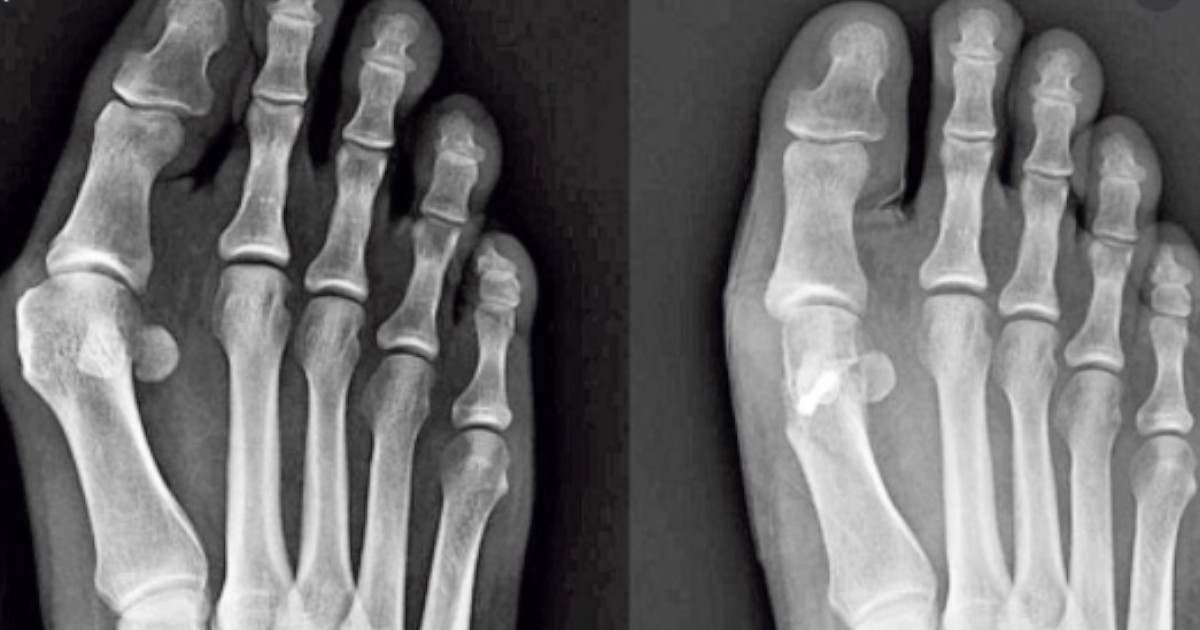

Haluks jest naroślą, która występuje z boku palucha u stopy. Jest przyczyną dyskomfortu u osób, które dotknął ten problem.

Paluch, czyli największy palec stopy jest swobodny względem innych palców. Jednak u osób z haluksami – paluch jest blisko palca obok, a rezultatem tego jest zmieniony wygląd stopy. Jest to schorzenie, które się rozwija i prowadzi do problemów w życiu codziennym.